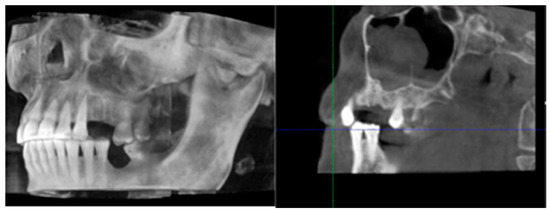

2. Materials and Methods

3. Results

4. Discussion

- Bedogni, A.; Fedele, S.; Bedogni, G.; Scoletta, M.; Favia, G.; Colella, G.; Agrillo, A.; Bettini, G.; Di Fede, O.; Oteri, G.; et al. Staging of osteonecrosis of the jaw requires computed tomography for accurate definition of the extent of bony disease. Br. J. Oral Maxillofac. Surg. 2014, 52, 603–608. [Google Scholar] [CrossRef]